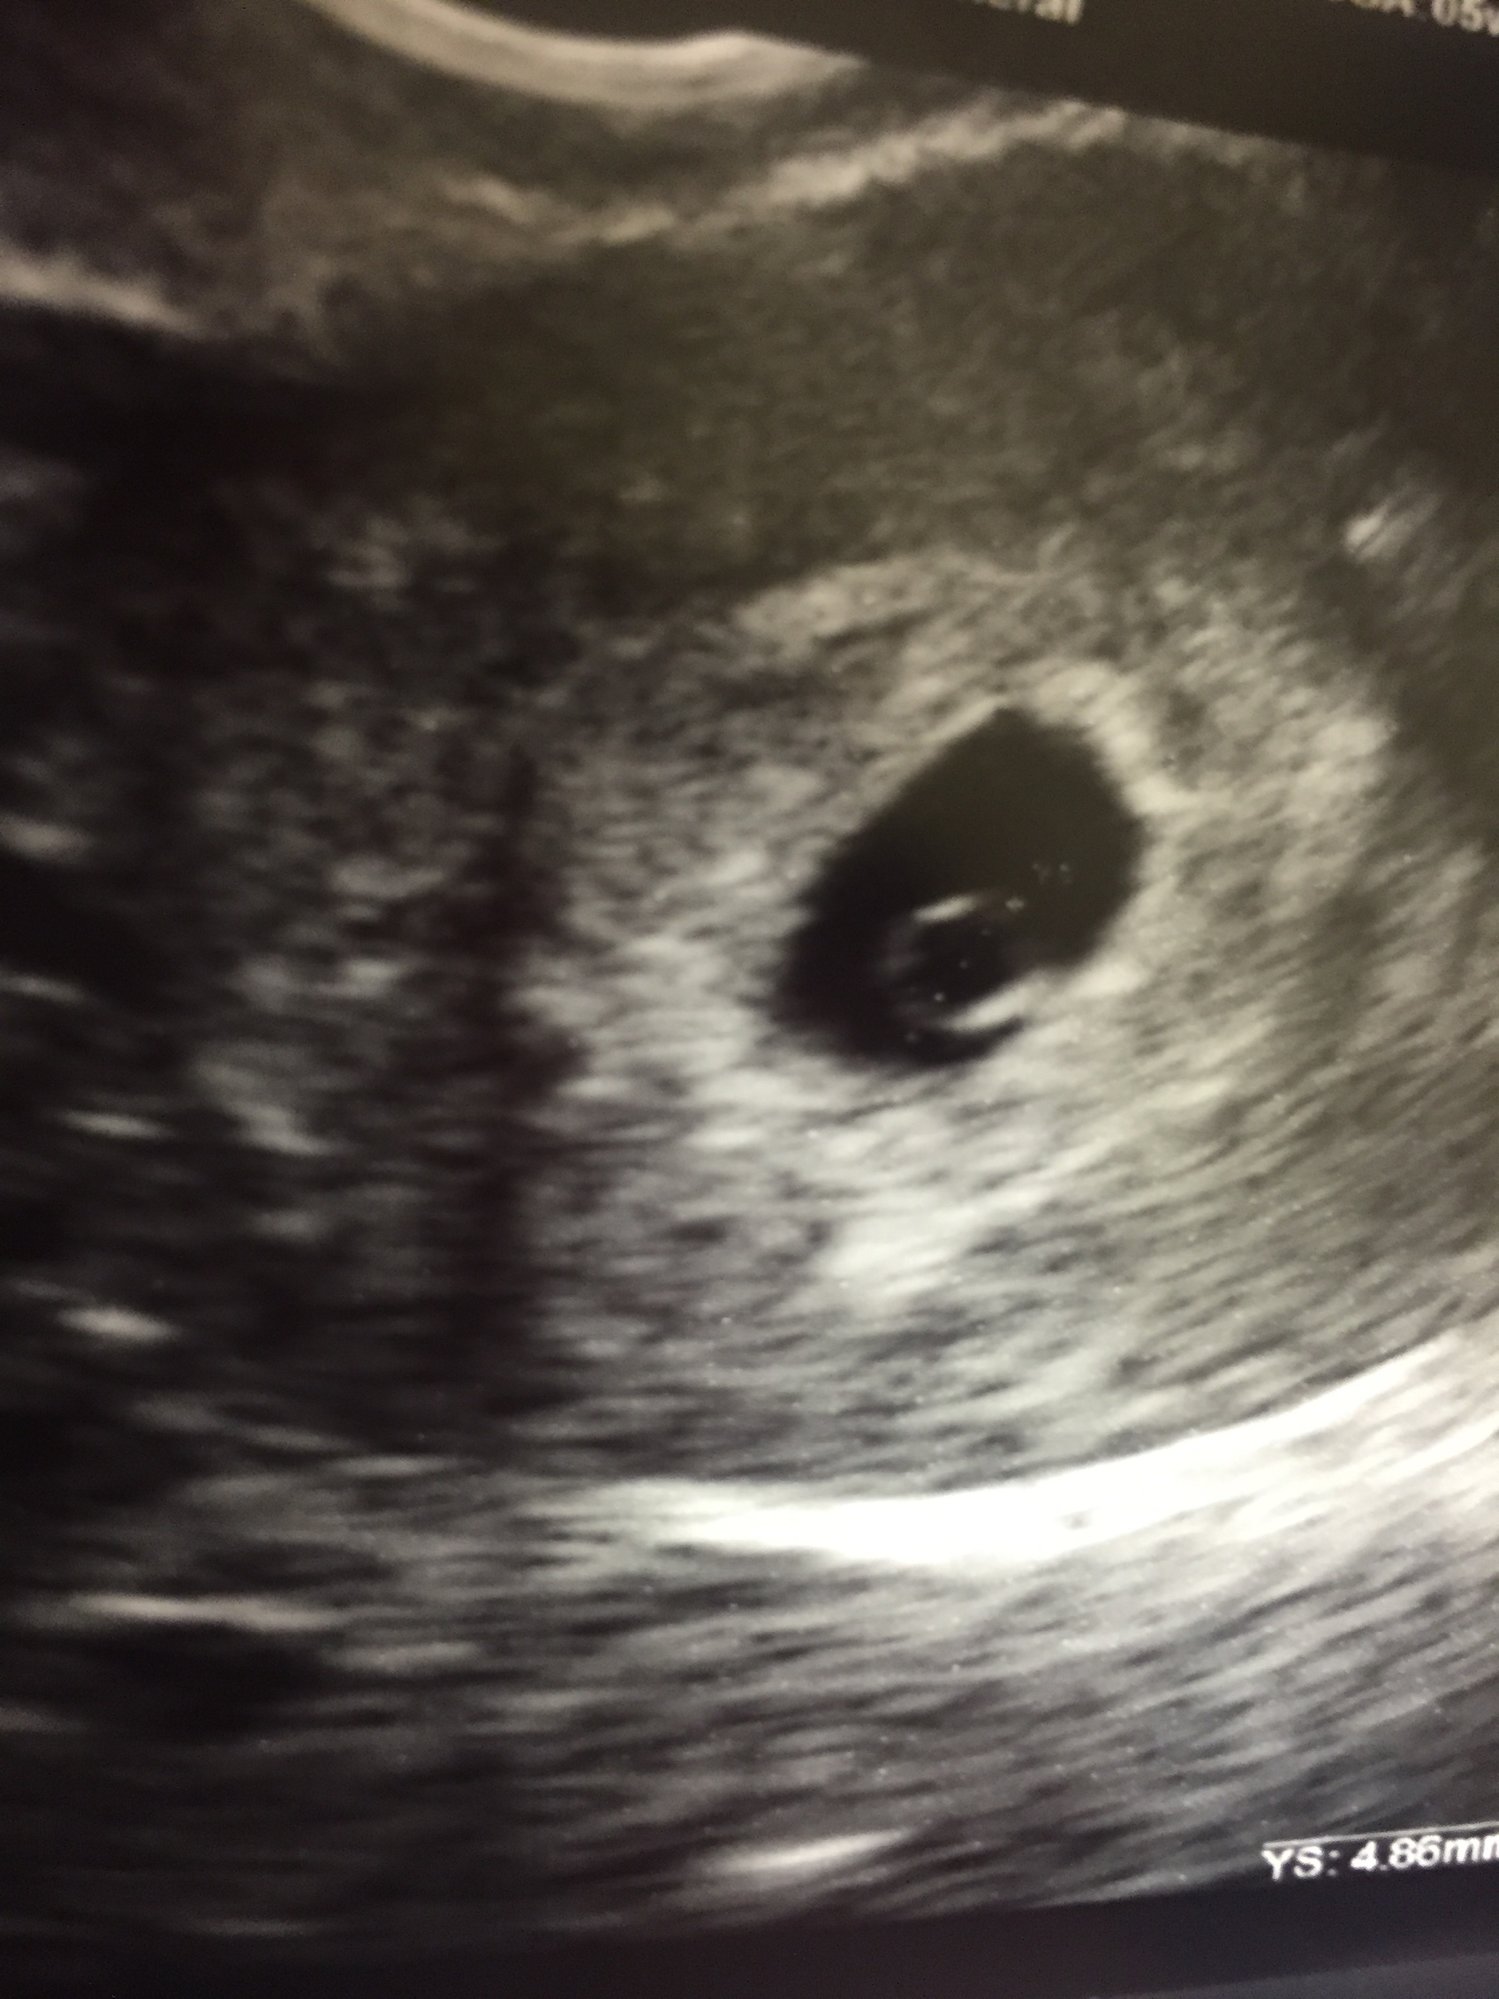

1st IUI 12/23/15 Clomid + Ovidrel - Beta 1/8/16 BFN 2nd IUI 1/22/16 Clomid + Ovidrel - Beta 2/8/16 BFN 3rd IUI 2/27/16 Clomid + Ovidrel - Beta 3/15/16 BFN 4th IUI 3/27/16 Clomid + Ovidrel - Beta 4/11/16 BFN 5th IUI 4/26/16 Clomid + Ovidrel - Beta 5/11/16 BFN *****TRIGGER***** 6th and final IUI 5/27/16 Clomid + Ovidrel - BFP!!! 1st Beta on 6/8/16 @ 12piui: 22; 2nd Beta 6/10/16 84.4; 3rd Beta 6/13/16 300; 4th Beta 6/16/16 1168; 5th and final beta 6/20/16 4188 1st U/S 6/23/16 - Two babies! One measuring 6w1d with a visible heartbeat!!! The other is measuring small and isn't likely to make it 2nd U/S 7/5/16 - Baby #2 didn't make it Baby #1 is measuring right on schedule and has a FHR of 143!! 3rd US 7/15/16 - Baby #1 right on schedule! FHR 168!!! Discharged from RE!!!!

1st U/S 6/23/16 - Two babies! One measuring 6w1d with a visible heartbeat!!! The other is measuring small and isn't likely to make it

2nd U/S 7/5/16 - Baby #2 didn't make it

3rd US 7/15/16 - Baby #1 right on schedule! FHR 168!!! Discharged from RE!!!!